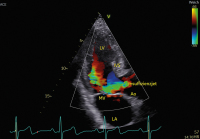

Aortenklappeninsuffizienz: Was gibt es Neues? // Aortic valve regurgitation – What do the 2021 guidelines say? What has changed from 2017?

Journal für Kardiologie - Austrian Journal of Cardiology 2024; 31 (5-6): 120-128 Volltext (PDF) Summary Abbildungen